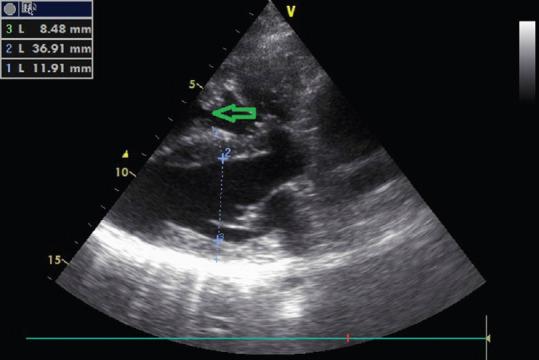

A double-chambered right ventricle (DCRV) is a rare congenital heart disease and an uncommon cause of congestive heart failure. An anomalous muscle band divides the right ventricle into two cavities: the proximal high-pressure chamber and the distal low-pressure chamber. Most cases are diagnosed and treated during childhood. Furthermore, there is a tendency for progression, if not treated early. Echocardiography is considered useful for the diagnosis of this ailment. Most of the patients have associated congenital anomalies, such as ventricular septal defect, pulmonary stenosis, and subaortic stenosis. Isolated DCRV is a rare entity. Hence, we report a case of an isolated DCRV in an adult patient.

双腔右心室(DCRV)是一种罕见的先天性心脏病,也是充血性心力衰竭的不常见病因。一条异常肌束将右心室分为两个腔:近端高压腔和远端低压腔。大多数病例在儿童期得到诊断和治疗。此外,如果不及早治疗,病情有进展的趋势。超声心动图被认为对诊断这种疾病有用。大多数患者伴有先天性异常,如室间隔缺损、肺动脉狭窄和主动脉瓣下狭窄。孤立性双腔右心室是一种罕见的情况。因此,我们报告一例成年患者的孤立性双腔右心室病例。